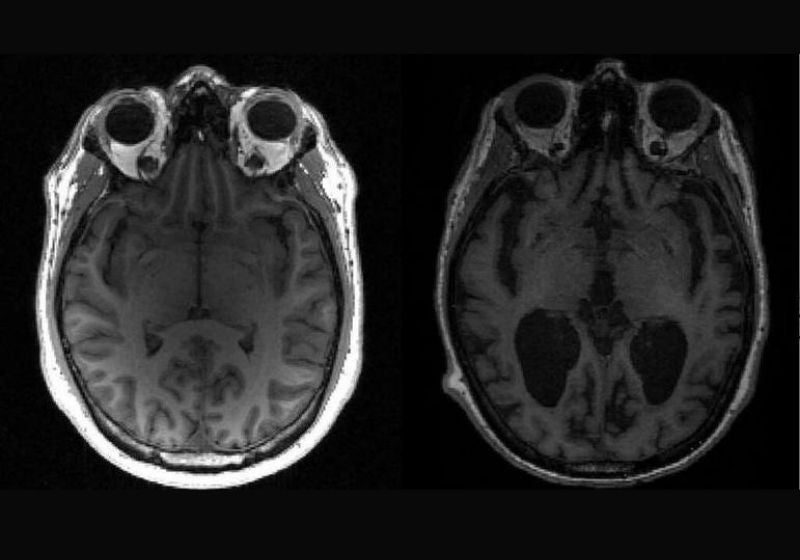

Os cientistas descobriram as causas do avanços do Alzheimer no cérebro humano - Foto: University of Cambridge/AFP

Na doença de Alzheimer, a tau e outra proteína chamada beta-amiloide se acumulam em agregados e fazem com que as células cerebrais morram e o cérebro encolha.